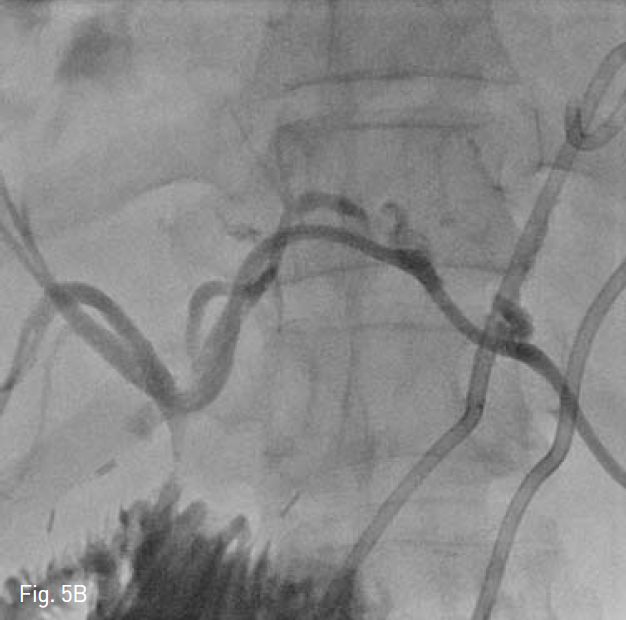

Fig. 5

After 20 days, the patient revisited our hospital with abdominal pain. We performed multiple percutaneous abscess drainage to both hepatic lobes A and left percutaneous biliary drainage B.